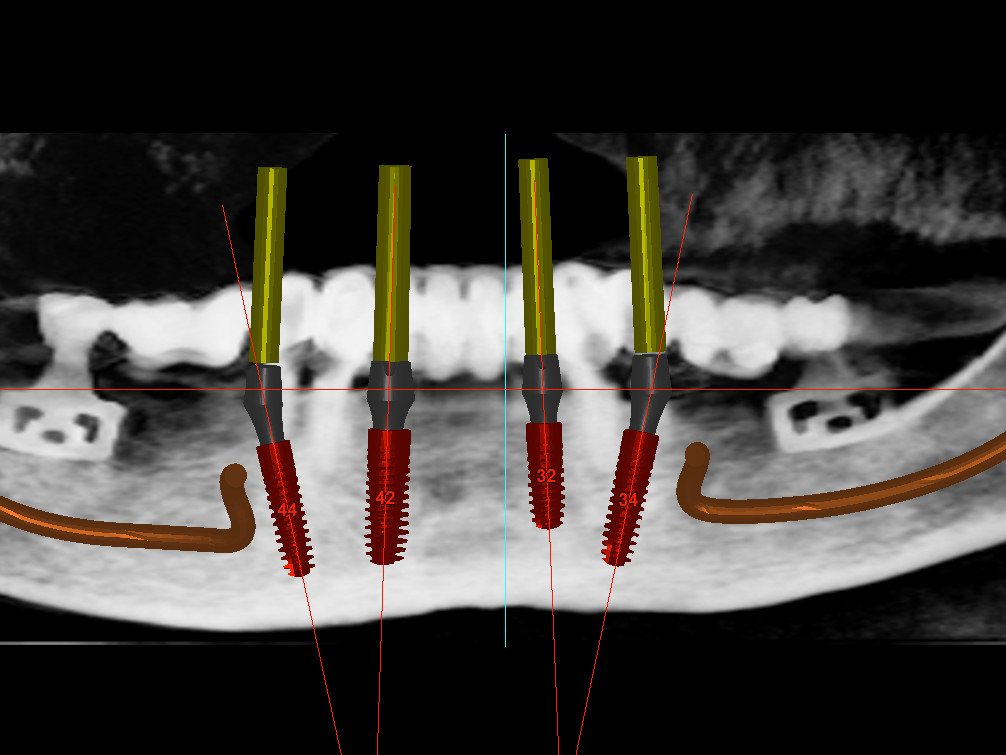

Bei dem nachfolgenden Fall handelt es sich um eine 73-jährige Nichtraucherin im guten allgemeinen Gesundheits- und Ernährungszustand. Die Patientin steht in keiner medikamentösen Behandlung und wies keine Allergien auf. Die Patientin kam 2012 zu uns in die Behandlung. Damals zeigte sich bei ihr eine festsitzende aber insuffiziente Rehabilitation im Unterkiefer, wobei die beiden Blattimplantate die gesamte Rekonstruktion trugen. Die Unterkieferzähne, die bisher die anteriore Abstützung bildeten, waren unter der prothetischen Versorgung kariös zerstört (Abb. 1). Seitens der Patientin bestand der Wunsch nach hochwertiger Rehabilitation des Unterkiefers möglichst mit einer Sofortversorgung. Eine zwischenzeitliche Versorgung mit einer schleimhautgetragenen Interimsprothese schied aus. Darüber hinaus war für die Patientin wichtig, eine möglichst geringe Belastung durch die anstehende Behandlung zu erfahren. Der Oberkiefer war mit eine herausnehmbaren Vollprothese rehabilitiert. Zur exakten Vorhersagbarkeit der Implantatpositionen wurde ein DVT angefertigt. Im Anschluss erfolgte eine gemeinsame Planung der chirurgischen sowie prothetischen Implantatposition im Team, bei der Chirurg, Prothetiker und Zahntechniker im ständigen Dialog standen (Abb. 2 und 3).

Für die Allgemeinanästhesie erfolgte zunächst die zusätzliche Gabe eines typischen Infiltrationsanästhetikums. Intravenös wurde unmittelbar präoperativ das Antibiotikum Clindamycin 600 mg gegeben. Abbildung 7 zeigt die klinische Ausgangssituation linksseitig. Nach der vorsichtigen Durchtrennung der Brückenkonstruktion (Abb. 8) jeweils vor der Krone auf den Blattimplantaten und Entfernung der nicht erhaltungswürdigen Zähne 44 bis 33 samt ihrer Überkronung (Abb. 9) wurde der Mukoperiostlappen vestibulär wie lingual passend zur erstellten Schablone präpariert und die Bohrschablone in ihrer finalen Lage eingebracht (Abb. 10). Zunächst erfolgte die Insertion der angulierten Implantate Ankylos ® C/X-Implantate (Durchmesser 3,5 mm) der Länge 14 mm in regio 034 (Abb. 11 und 12) und 044. Danach wurden in den Positionen 032 und 042 jeweils ein weiteres Ankylos ® C/X –A-Implantat mit gleicher Länge und Durchmesser inseriert (Abb. 13). Sämtliche entfernten Knochenpartikel und auch Bohrspäne wurden akribisch asserviert. In den Positionen 032 und 042 wurden Ankylos ® Balance Basisaufbauten C/ (GH 3,0 / Ø 5,5 mm, Kopfhöhe 2,4 mm) mit 15 N/cm eingeschraubt. Anschließend hat der Zahntechniker mittels der Ankylos ® Modellierhilfskappenfür den Balance Basisaufbau Retentionskappen hergestellt, die mit 25 N/cm eingebracht wurden (Abb. 14). Am Implantat regio 042 wurde der Knochen in Schalentechnik nach vestibulär aufgebaut (Abb. 15)⁹,¹⁰. Im nächsten Schritt haben wir die angulierten Ankylos ® Balance Basisaufbauten C (nicht indexierte Abutments) in Regio 034 und 044 (GH 3,0, A30 / Ø 4,2 mm, Kopfhöhe 1,3 mm) ausgerichtet und ihren spezifischen Vorgaben entsprechend eingebracht (Abb. 16). Nachdem sich alle erforderlichen prothetischen Implantatbauteile in situ befanden (Abb. 17), erfolgte die Überprüfung und geringfügige Anpassung des im Vorfeld digital erstellten Sofortprovisoriums. Im Anschluss wurden die leeren Alveolen und Knochendefekte mit dem gewonnenen autologen partikulären Material aufgefüllt. Dann erfolgte der typische Naht-Wund-Verschluss mit Einzelknopfnähten eines resorbierbaren Nahtmaterials (Abb. 18). Nachdem die Patientin aus der Vollnarkose erwacht war und ihre motorischen Fähigkeiten wiedererlangt hatte, wurde das Sofortprovisorium eingesetzt und in Okklusion gebracht. In dieser Position wurden die Retentionskappen über ein selbsthärtendes fluoreszierendes kaltpolymerisierendes Paste-Kartuschensystem fixiert. Anschließend erfolgte die extraorale Versäuberung des Interimszahnersatzes. Nach Refixierung des Sofortprovisoriums in der Mundhöhle (Abb. 19 und 20) und dem Verschluss der Schraubenkanäle mit Kunststoff erfolgte die radiologische Kontrolluntersuchung (Abb. 21).